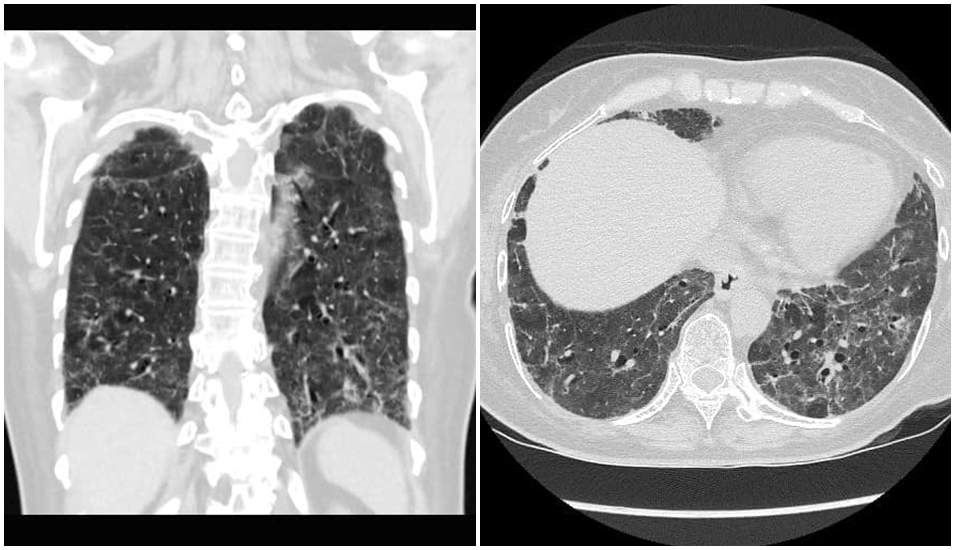

醫師蘇一峰今天在臉書貼出COVID-19確診重症病患「肺纖維化」的照片,表示病人現在無法脫離氧氣,而這樣的情況出現在院內自己人身上,讓他非常難過,還透露昨天打了好幾通電話想辦法。

蘇一峰心痛呼籲,「高危險醫護人員趕快打疫苗,不想肺纖維化就趕快打疫苗」,他也在留言處表示,很多醫護人員第一劑都是打AZ疫苗,要等2個月才能打第二劑,有些醫護等待的中間就被感染了,如果可以混打只要等1個月就好。」

(取自蘇一峰臉書)